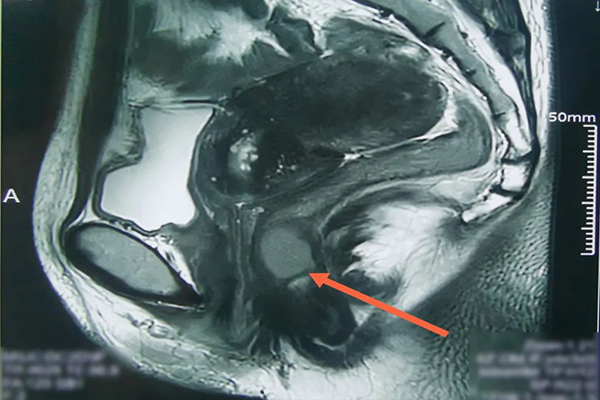

39岁的宋女士经常感觉肛门坠胀不适,后期出现排便困难,自认为是痔疮,并没有引起重视。久而久之,坠胀感和排便困难愈发严重,宋女士就医后被诊断为低位直肠间质瘤。胃肠间质瘤是一种容易被忽视的恶性肿瘤,随着时间推移,几乎所有的胃肠间质瘤都会出现恶性行为,如变大、转移、术后复发等。宋女士辗转了多家医院,均被告知需要手术治疗而且很可能保不住肛门,她无法接受,几乎想放弃治疗。当了解到第一医院北院肛肠科在治疗肛门直肠肿瘤方面有丰富的临床经验,她便再次鼓起勇气来到了医院。入院后经核磁显示:距肛缘约2cm处,位于直肠下段-肛管右侧壁有一类圆形阴影。随后医生进行肛门指检,发现截石位7-11时位,有一直径约4cm×3cm×3cm的直肠粘膜下肿物,距离肛门较近。